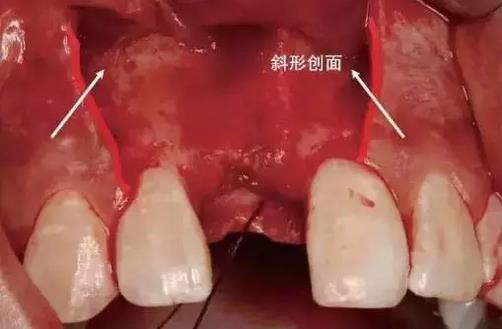

第三步:行縱向切口,從齦溝底向齦緣運(yùn)刀,避開(kāi)牙齦乳頭,止于軸面角,形成外斜切口(圖)。

縱向切口應(yīng)做成斜形創(chuàng)面(斜面向外)